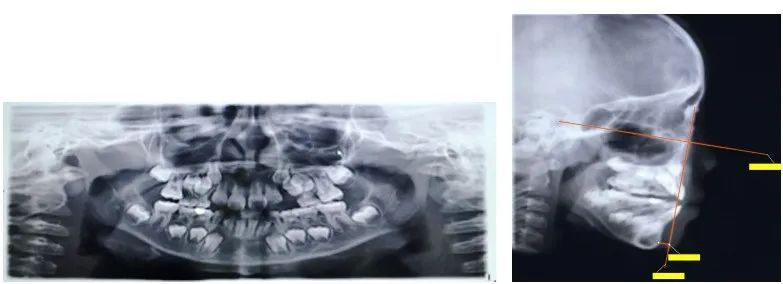

比如说这个孩子初诊时为替牙期,前牙对刃,但是患者家长拒绝接受矫正干预,一年半后复诊,前牙反颌重,并出现下颌前突。

首先要观察下颌骨形态。如果是高角,这种反颌难做,需要很多时间。如果是均角或者低角,矫治效果好而且稳定,不容易复发。

如果是上颌后缩,这种反颌也相对好做一些。但是如果是下颌前突,这种情况很差,下颌骨可能会随着生长越来越前突,反颌可能会加重。